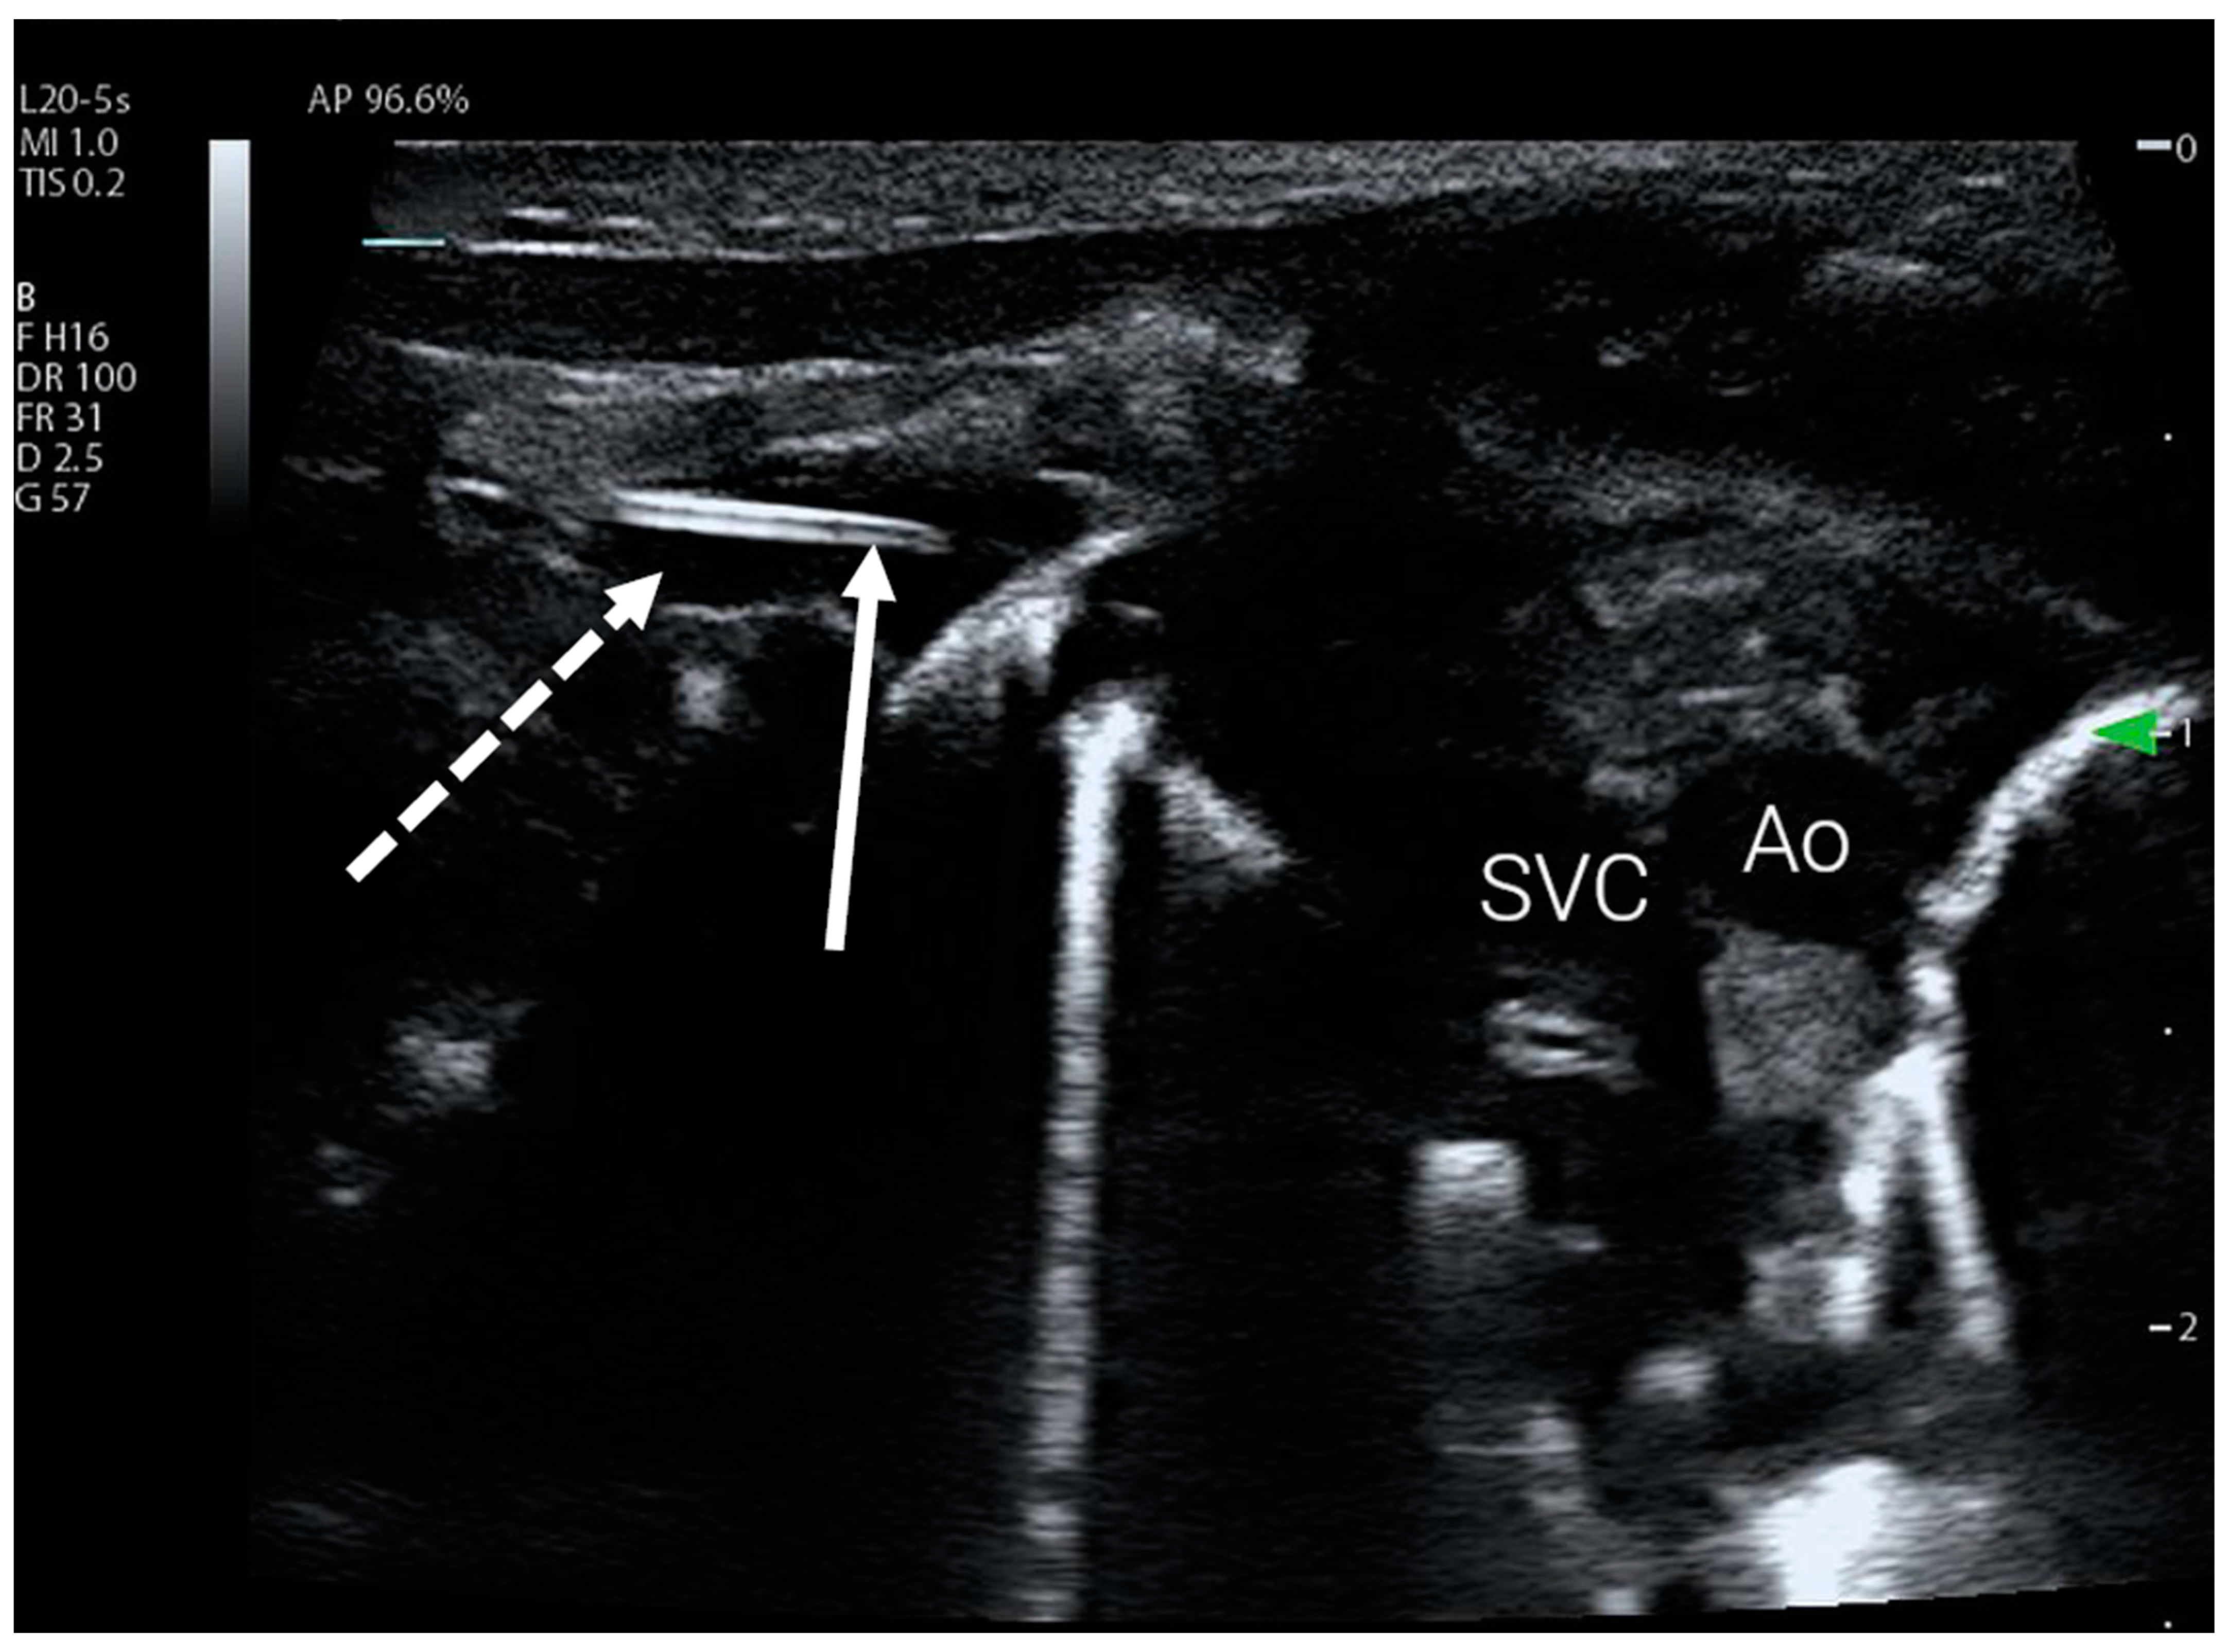

Figure 2.

PICC catheter tip visible in the subclavian vein using subclavian view. The subclavian vein is marked with a dotted arrow, full arrow indicates catheter tip. Ao—aorta, SVC—superior vena cava.